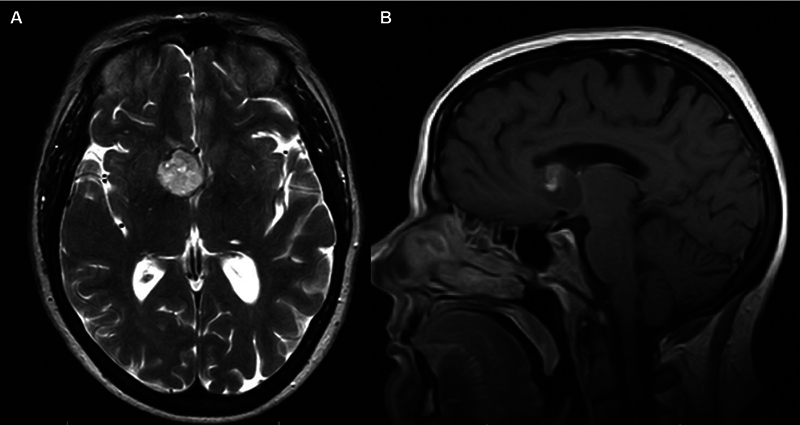

背景:室管膜下巨细胞星形细胞瘤(SEGA)是一种发生于室管膜下组织的罕见肿瘤。SEGA主要与结节性硬化症(TSC)相关,可表现为一系列不同的症状,最常见的是癫痫发作或TSC的神经皮肤特征。我们提出一个新病例散发性SEGA在一个59岁的妇女谁提出了急性肝实质内出血(IPH)。方法系统查阅文献,结合案例分析。结果1例59岁女性患者表现为头痛,意识水平下降,急性IPH累及前隔透明膜和右侧内侧尾状头。MRI提示有潜在的肿瘤,后续影像学显示肿瘤生长缓慢,需显微手术切除。术后病理证实SEGA (WHO I级),无TSC1/2突变。随访1年,患者无疾病,神经功能完整。一项系统综述确定了7篇出版物,在9名无TSC的成年患者中病理证实了SEGA。头痛、乳头水肿和视觉障碍是最常见的症状。治疗方案包括显微手术切除与活检后的放射学监测,截至最后一次随访,总体无症状生存率至少为80%。结论:我们报告了第10例散发性SEGA成人患者,无TSC,并对这种罕见的肿瘤实体进行了相关的系统回顾。需要进一步的研究来确定散发性SEGA发展的危险因素,以及可能偏离儿童TSC患者标准方案的这种疾病管理的潜在途径。

Background  Subependymal giant cell astrocytoma (SEGA) is a rare neoplasm arising from subependymal tissue. Predominantly associated with the tuberous sclerosis complex (TSC), SEGA may present with a range of diverse symptoms, most commonly seizures or neurocutaneous features of TSC. We present a novel case of sporadic SEGA in a 59-year-old woman who presented with acute intraparenchymal hemorrhage (IPH). Methods  Systematic literature review and illustrative case example. Results  A 59-year-old woman presented with a headache decreased level of consciousness, and acute IPH involving the anterior septum pellucidum and right medial caudate head. MRI was concerning for an underlying neoplasm, which grew slowly on follow-up imaging, prompting microsurgical resection. A gross total resection was achieved, and postoperative pathology confirmed SEGA (WHO grade I) without TSC1/2 mutation. She remained disease-free and neurologically intact at 1-year follow-up. A systematic review identified seven publications that revealed pathologically confirmed SEGA in nine adult patients without TSC. Headache, papilledema, and visual disturbances were the most common presenting symptoms. Treatment protocols included microsurgical resection versus biopsy followed by radiographic surveillance, and the overall rate of symptom-free survival was at least 80% as of the last follow-up. Conclusion  We report the tenth case of sporadic SEGA in an adult patient without TSC, as well as an associated systematic review of this rare neoplastic entity. Further study is required to identify risk factors for the development of sporadic SEGA, as well as potential avenues for the management of this disease that may depart from the standard protocol in pediatric TSC patients.